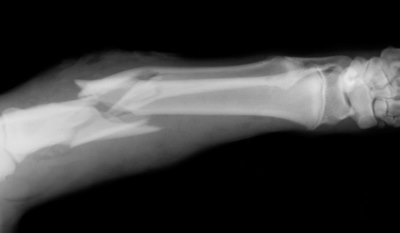

Today we can go to the doctor, get an xray and find out if we broke a bone or just sprained it. In an SHTF situation, we probably won’t have a xray machine in our bug out bag, It helps to understand the symptoms of these injuries and how they differ.

The two main categories of fractures are displaced, non-displaced (open, and closed) Displaced and non-displaced fractures refer to the way the bone breaks.

A non-displaced fracture is when the bone is broken into pieces that can be aligned in place.

A displaced fracture is when the bone is broken into pieces that do not align properly.

Some other categories of breaks include…

- Hairline fracture: The bone is broken in a thin crack.

- Single fracture: The bone is broken only in one place.

- Compression fracture: The bone is basically crushed.

- Comminuted fracture: The bone is crushed or broken into three or more pieces.

- Segmental fracture: The bone is broken in two places, which leaves at least one bone segment floating and unattached.

A compound fracture or an open fracture is when the bone breaks through the skin. The bone may or may not be visible because the bone could recede back into the wound not be visible through the skin.

It’s important to remember that with an open fracture there is a risk of a deep bone infection.

A displaced fracture: happens when the bone snaps into two or more parts and moves so that the two ends are not lined up straight. These are also known as complete fractures.

A non-displaced fracture: is when the bone cracks either part or all of the way through, but does move and maintains its proper alignment. These are also known as incomplete fractures.